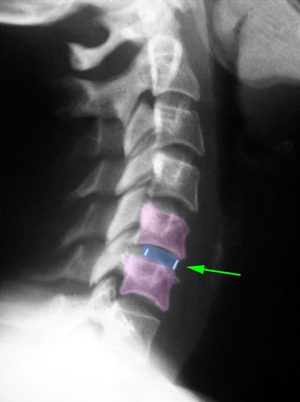

Πρόσθια αυχενική δισκεκτομή και σπονδυλοδεσία με κλωβό από PEEK (μπλέ) Α5-Α6.

AntCervFusPlat

Πρόσθια αυχενική δισκεκτομή Α4-Α5, Α5-Α6, Α6-Α7 και σπονδυλοδεσία με κλωβούς από PEEK (μπλέ) και πλάκα με βίδες Α4-Α7 (ροζ)